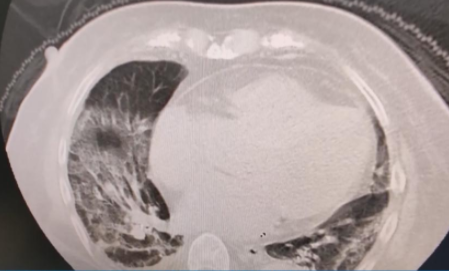

The health condition of Pele, the 82-year-old legend of Brazilian football, has deteriorated significantly in recent days. 82岁的巴西足球传奇人物贝利(Pelé)的健康状况最近几天明显恶化。 One of the greatest football players in the world has been fighting colon cancer for a long time and spent the Christmas holidays in the Albert Einstein Hospital. 这位世界上最伟大的足球运动员之一长期与结肠癌作斗争,并在阿尔伯特·爱因斯坦医院度过了圣诞节假期。 Pele was admitted to the hospital on November 29. The legendary Brazilian made his last public appearance on Instagram when he congratulated Lionel Messi and Argentina on winning the 2022 FIFA World Cup in Qatar. 贝利于11月29日入院,这位巴西传奇人物最后一次在Instagram上公开露面,是祝贺莱昂内尔·梅西(Lionel Messi)和阿根廷赢得2022年卡塔尔世界杯冠军。 A clip is circulating on social media that reveals how serious Pele’s condition is. He said goodbye to his family and friends from his hospital bed. In the video, it can be seen that he is talking to his family on the phone with great effort. 社交媒体上流传着一段视频,可以看出贝利的病情非常严重。他在病床上向家人和朋友道别。在视频中,他正在努力地与家人通电话。The hospital announced that the disease is progressing and that he needs further care in order to avoid further possible heart problems.医院宣布贝利的病情正在恶化,需要进一步治疗,以避免更严重的心脏问题。 His daughter previously confirmed that Pele will spend the festive season in hospital with his family.此前,他的女儿证实,贝利将与家人一起在医院度过这个圣诞节。 “We always have a lot to be thankful for, even if we spend Christmas in hospital, knowing what a privilege it is to be in a hospital like the Albert Einstein Hospital. “尽管我们今年在医院度过这个圣诞节,但我们总是有很多值得感谢的事情,因为我们知道能在阿尔伯特·爱因斯坦医院治疗是多么的荣幸。 It’s really nice to see our father being treated by the professionals who they are extremely loving at the same time. Let us not for a moment forget that privilege. Even in sorrow we must be grateful. 看到父亲能够受到专业人士的治疗我们真的很高兴,他们非常有爱心。让我们永远铭记这份幸运。即使处在悲伤中,我们也必须心存感激。 Thank you for being together, thank you for all your love, thank you for being here with us now. Merry Christmas. Much health, much love, much joy, much laughter and much passion, today and always, to all of you."谢谢你们的陪伴和爱,谢谢你们一直与我们同在。圣诞快乐,无论是今天还是永远,都祝你们所有人健康、幸福、快乐、充满热情。” Some COVID-19 patients were found to have pneumonia or their CT scans showed they had "white lungs" recently.从近期的公众反映情况看,有的新冠病毒感染者在就诊过程中发现了肺炎或者是CT出现了白肺的现象,有网友认为,出现这种情况可能是跟感染了原始毒株或者接种疫苗有关系的。 Now the so-called "white lungs" have nothing to do with the original strain or vaccination, and Omicron is still the dominant strain, Jiao Yahui, a senior official with the National Health Commission, said at Tuesday's press briefing.国家卫健委的高级官员焦雅辉在周二的新闻发布会上表示:现在出现的所谓“白肺”与原始毒株和疫苗接种没有关系,当前的流行优势毒株仍然是奥密克戎毒株。 白肺(White Lung)是肺部影像学表现的一个口语化描述。当出现炎症和感染,肺泡被渗出液等填充,在影像学上的表现就是出现白色区域。并不是只要肺部出现了炎症就都叫白肺,一般来讲肺部炎症较重、渗出液较多,白色的影像区域面积达到70%—80%时,在临床上把它称为白肺。 Beijing CDC researcher Pan Yang said the virus subvariants circulating in Beijing are the Omicron subvariants BF.7 and BA.5.2. 北京疾控中心研究员潘阳说,在北京流行的病毒亚型是奥密克戎亚型BF.7和BA.5.2。 No XBB, BQ.1 or other variants were found in Beijing communities, and non-Omicron variants such as the original strain and Delta strain were not detected, said Pan, according to Beijing Daily.在北京社区未发现XBB、BQ.1或其他变异株,据《北京日报》报道,潘阳表示,没有检测到原始株、德尔塔等非奥密克戎变异株。 Wuhan, Central China's Hubei Province, has carried out sampling and monitoring in two sentinel hospitals once a week, collecting 20 throat swab samples each time.中国中部的湖北省武汉市每周对两所哨点医院进行一次采样和监测,每次采集20份咽拭子样本。 In December, the samples were increased to 40 each time, and Wuhan Jinyintan Hospital was added as a sampling sentinel hospital this week, according to the Hubei authorities on Tuesday.据湖北当局周二称,12月份,每次抽样数量增加到40个,本周又增加了武汉金银潭医院作为哨点医院, The monitoring data indicate that Omicron BA.5.2 is still the variant circulating in Wuhan.监测数据表明,奥密克戎BA.5.2仍是武汉地区流行的变种。 Since October, all the viruses detected in the collected samples were BA.5.2 variant strains, and no other types of strains were found, Yang Xiaobing, an official with the Wuhan CDC, said on Tuesday.自10月份以来,收集的样本中检测到的病毒均为BA.5.2变异株,未发现其他类型的毒株,武汉市疾控中心的一名官员杨小兵周二表示。 As for the public's question over whether people will be reinfected, Wang Guiqiang, director of the infectious diseases department at Peking University First Hospital,对于公众关于会不会再次感染的问题,北京大学第一医院传染病科主任王贵强接受新华社记者采访时表示, told Xinhua that for the vast majority of people with normal immunity, there will be effective immune antibodies for half a year, and the probability of reinfection from the same strain is very low.对于绝大多数免疫正常的人来说,半年内都会有有效的免疫抗体,而来自同一菌株的再次感染的可能性非常低。 However, reinfection may occur if a new mutant or subvariant shows strong immune escape ability, so Wang suggested the public still be cautious after this wave of outbreaks.然而,如果一个新的突变体或亚变异体表现出很强的免疫逃逸能力,就可能发生再次感染,因此,王贵强建议公众在这波疫情爆发后仍需谨慎。 素材来源:Global Times、Fortune